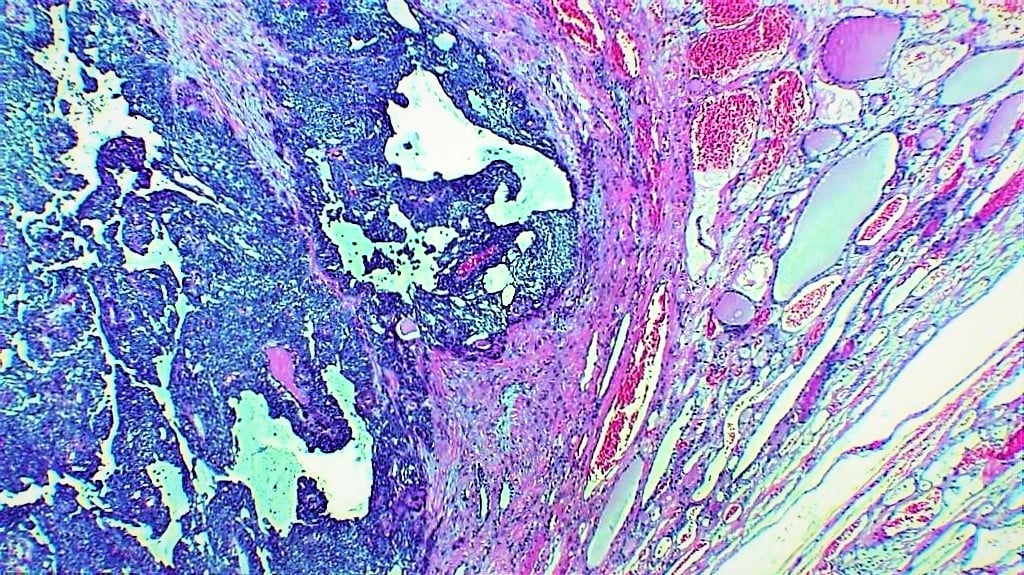

First Place

Gary Hammer — University of Michigan, Ann Arbor, Mich.

The adrenal gland is a critical organ that not only mounts the "flight or fight" stress response, but also is required for proper salt and carbohydrate balance. Shown at the top is a histological section of the mouse adrenal gland. The red area marks the adrenal cortex, containing cells that produce aldosterone, cortisol and glucocorticoids. Yellow cells are remaining cells of the fetal adrenal cortex. The blue core of the adrenal is the medulla, the region where epinephrine (adrenaline) is produced. In the middle and bottom images, the image of the adrenal has been manipulated using Photoshop filters.